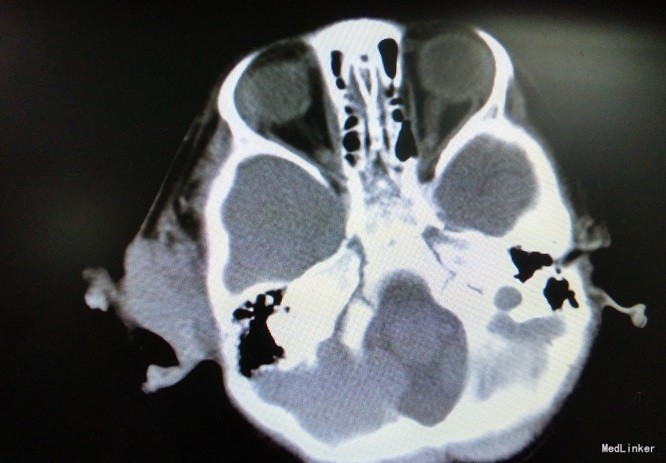

主诉:男,3岁,确诊“横纹肌肉瘤”7月,拟化疗 病史:入院前7月患儿因右耳前包块于我院行细针穿刺活检术,术后免疫组化提示胚胎型(间变型)横纹肌肉瘤。术后于我院就诊,完善胸部增强CT、腹部彩超、浅表淋巴结超声、骨髓涂片等检查后诊断为横纹肌肉瘤(胚胎型,间变型,Ⅰ型),首次予以IVA方案化疗。后于我院规律化疗,右耳前包块较前有所缩小。3月前行“右面部横纹肌肉瘤扩大切除术+右腮腺部分切除术+右颈部轴形瓣转移修复术”术中冰冻切片提示边界均未见肿瘤细胞,术后病理检查支持横纹肌肉瘤诊断,FISH未检出有意义的FOX1(FKHR)基因易位。末次按IVA方案给予异环磷酰胺、长春地辛、更生霉素化疗。现患儿一般情况可,无发热、咳嗽、呕吐、腹泻等不适,拟化疗入院。末次化疗以来,体重增加1Kg。

查体:右侧耳前可见一长约4cm手术切口瘢痕,愈合良好。 辅检:血常规:WBC 12.3×109/L 、N:11.96×109/L,Hb90g/L,PLT42*10^9;CRP:130mg/L,心电图示:窦性心律不齐,电轴左偏-1°,心电图大致正常。血培养示:粘质沙雷菌、产酸克雷伯菌,对亚胺培南敏感。

诊断:横纹肌肉瘤(胚胎型,间变型,Ⅰ型) 处理:异环磷酰胺、长春地辛、放线菌素D化疗,辅以水化碱化、止吐、美司钠,复合辅酶护心、护肝,止血敏改善血小板功能,泰能抗感染,丙球支持等。